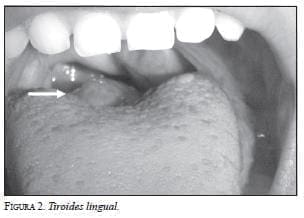

Se hizo una resonancia magnética de base de cráneo y silla turca (figura 3), que demostró, en el tercio posterior de la lengua, una pequeña lesión levantada de 15 mm de diámetro mayor, redondeada, con señal ligeramente baja en secuencia de T1 y ligeramente alta en secuencia de T2, no definida con claridad debido a su localización, ya que el movimiento respiratorio interfería con la señal. La lesión en la base de la lengua era sugestiva de tiroides lingual, por lo cual se recomendó complementar su estudio con una gammagrafía de tiroides.

El estudio gammagráfico se realizó 24 horas después de la ingestión de 10 μCi de yodo radioactivo (I131) (figuras 4 y 5). Se obtuvieron imágenes estáticas de la región cervical anterior, y laterales de derecha e izquierda con un equipo ADAC Single Head, matriz de 128 x 128 x 16, de campo total (full field), durante 300 segundos; las imágenes se procesaron en un computador Pegasys Epic. No se observó concentración del trazador en la región donde normalmente se localiza la glándula tiroides; sin embargo, se notó un área focal de concentración de yodo radioactivo en la boca localizada en el aspecto posterior de la lengua, lo que sugería, en primera instancia, una glándula tiroides ectópica lingual. La captación de I131 en 24 horas fue de 12,38% (valor normal, por encima de 16%), por lo que se recomendó hacer la correlación con la clínica y con los niveles séricos de hormonas tiroideas.